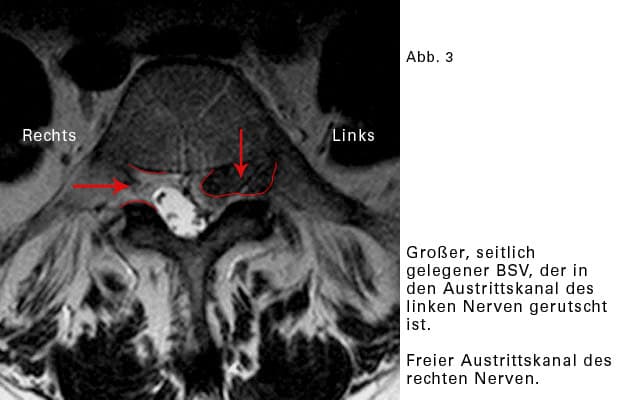

Seitlicher BSV:

Der Riss des Faserringes liegt seitlich, rechts oder links. Der Vorfall rutscht in den seitlichen Teil, und zwar in den knöchernen Austrittkanal eines Nerven. Hier ist relativ wenig Raum, und eine Quetschung der Nervenwurzel eher wahrscheinlich.